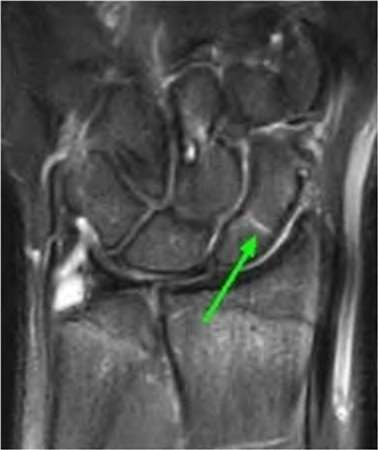

A 22-year-old male falls onto an outstretched hand and sustains a displaced fracture through the proximal pole of the scaphoid. Avascular necrosis of the proximal pole is highly likely due to the disruption of its primary vascular supply. Which vessel provides this critical retrograde perfusion?

Explanation

The primary blood supply to the scaphoid is from the dorsal carpal branch of the radial artery, which enters the dorsal ridge of the scaphoid at the waist and courses proximally. This retrograde blood flow makes proximal pole fractures highly susceptible to avascular necrosis and nonunion. The superficial palmar branch provides a minor supply (about 20%) to the distal pole.